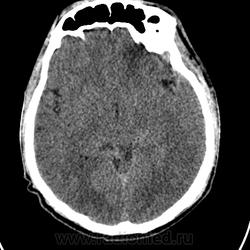

Доброе утро, уважаемые коллеги! Ночью привезли молодого человека с ДТП. Находится  в коме, множественные переломы лицевого скелета. Помогите описать их. Спасибо.

Надежда, а отека мозга нет?Мне показалось, что сглаженность борозд, сужение межгиральных пространств все же есть.Но не судите строго-в КТ пока не очень.

Интракраниально: срединные стрктуры не смещены, цистерны основания мозга не деформированы, желудочки симметричны, латеральные щели и конвекситальные борозды проослеживаются с обеих стророн. Есть снижение плотности белого вещества левой лобной доли (ушиб I вида (по Корниенко).

Однозначно, тут есть и перелом основания черепа (тело и большое крыло основной кости), а также небольшие эпидуральные гематомы в области кавернозного синуса и передних отделов средней черепной ямки. Так что, без нейрохирургов не обойтись...